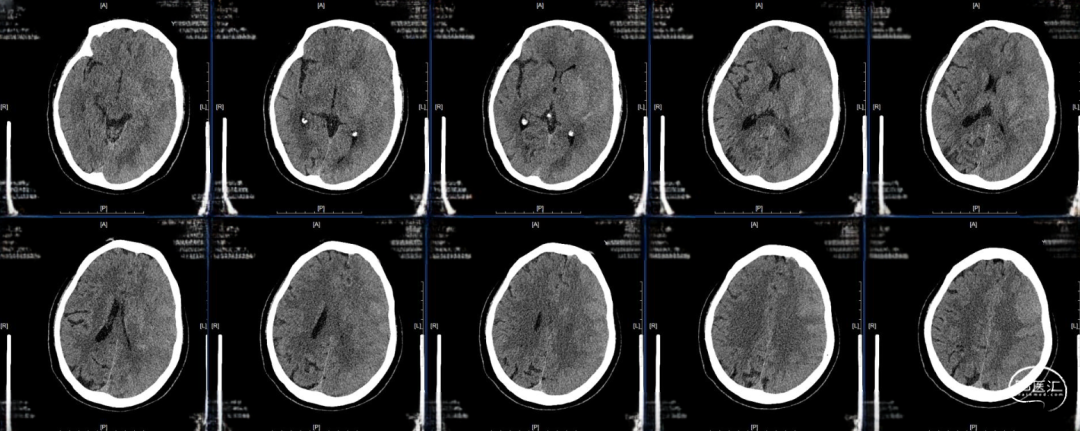

术后即刻DynaCT

术后24小时复查CT,高灌注、轻肿胀,未见明显出血,轻度镇静至停用镇静,过程中可唤醒,自然复苏,呼吸机维持。

术后48小时复查CT,左半球大片低密度病灶、中线偏移,有主动睁眼、遵嘱动作,暂停呼吸机,延迟拔管,备去骨瓣。

术后96小时复查CT,左侧半球肿胀未继续进展,嗜睡,易唤醒、有睁眼、遵嘱动作,右侧肢体有自主动作,拔除气管插管。

术后第14天启动抗凝,术后第19天复查CT,术后第20天出院,NIHSS评分8分,mRs评分4分。